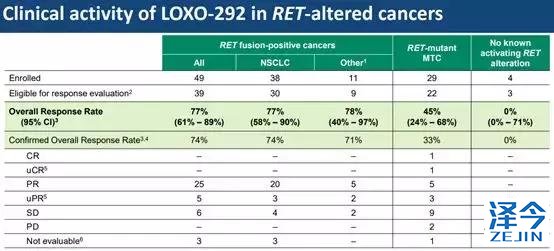

共有82名患者接受了7组LOXO-292治疗,剂量范围从每天20mg到240mg,每天两次。该研究招募的患者均为RET融合阳性癌症患者或RET突变患者。为RET融合阳性包括38例NSCLC患者,9例甲状腺乳头状癌,2例胰腺癌。RET突变组仅包括甲状腺髓样癌患者(n = 29)。

在带有RET融合变异的患者中,LOXO-292的总体缓解率为77%。其中,非小细胞肺癌的总体缓解率也为77%。而在RET变异的甲状腺髓样癌中,这款在研新药的总体缓解率为45%。此外,这款新药还展现出了持久的疗效。首名参与此研究的非小细胞肺癌患者,持续缓解时间已经超过了10个月。